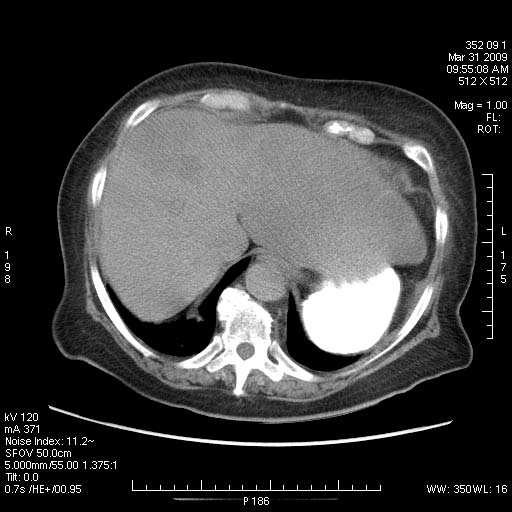

Женщина 82 лет с болями в эпигастральной области.

Такие метастазы в печень очень хорошо видны на поздней артериальной/портальной фазе, с типичным периферическим усилением по типу "кольца".

Заблуждение № 2. «УЗИ является прекрасным методом диагностики метастазов печени». Крайне опасное заблуждение. По современным данным выявляемость метастатических очагов до 3 см при обычном УЗИ может не превышать 45 %, более 3 см – 80 %. Чувствительность УЗИ может быть существенно повышена применением ультразвуковых контрастных средств, однако последние очень дороги и требуют современного ультразвукового оборудования. Вывод: при необходимости выявления очаговых поражений печени необходимо выполнение протоколов КТ. Для уточнения природы выявленных очагов возможно проведение прицельной биопсии под контролем УЗИ.

The accuracy of unenhanced US in the assessment of hepatic metastases is lower than that of contrastenhanced CT and MR. In series with a true gold standard, its sensitivity ranges between 50% and 76% (Table 18.2) (Clarke et al. 1989; Ohlsson et al. 1993; Wernecke et al. 1991). Problems encountered with US are its operator-dependent nature (making it difficult to use for follow-up staging), the sometimes difficult access to subdiaphragmatic areas of segments IVa and VIII and poor liver-to-lesion contrast of isoechoic lesions, especially in small metastases. For lesions smaller than 1 cm, the false-negative rate is as high as 80% (Wernecke et al. 1991). The false-positive rate of US is in the order of 5–10% on a by patient basis and considerably higher on a by lesion basis.